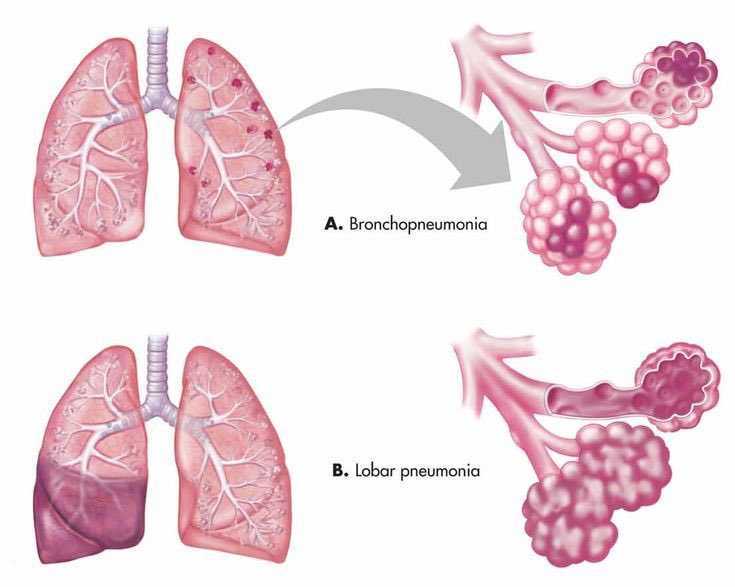

Медицинская тема: легочные осложнения при пневмонии